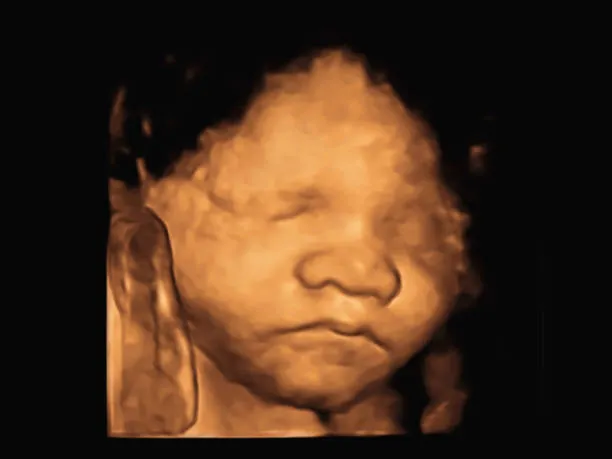

Upload your ultrasound

Get your baby's portrait

Convert any ultrasound to a baby photo - works with all pregnancy stages and ultrasound types

Transform your ultrasound image into a realistic baby portrait in 3 simple steps

Drag and drop or click to upload any 2D or 3D ultrasound photo from your phone, computer, or cloud storage.

Our advanced AI analyzes facial features in your ultrasound and generates a realistic portrait showing what your baby might look like.